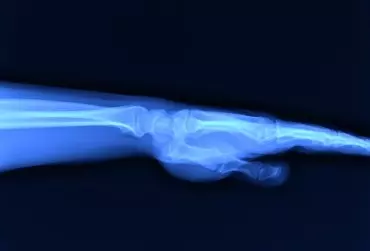

Diagnostyka różnicowa zespołów bólowych kończyny górnej - część 2

Dolegliwości bólowe w obrębie kończyny górnej mogą mieć różną przyczynę, dlatego tak ważna jest diagnostyka różnicowa. W ustaleniu prawidłowego rozpoznania pomocne jest tradycyjne badanie radiologiczne, które pozwala na wykrycie wielu patologii, takich jak urazy, zmiany zwyrodnieniowe, przeciążeniowe, choroby metaboliczne, zapalne i nowotwory, choć ma też swoje ograniczenia.